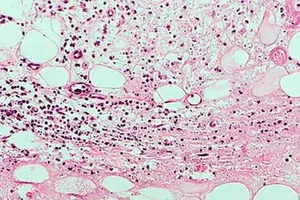

Úc đau đầu với đại dịch “loét ăn thịt” ngày một lan rộng